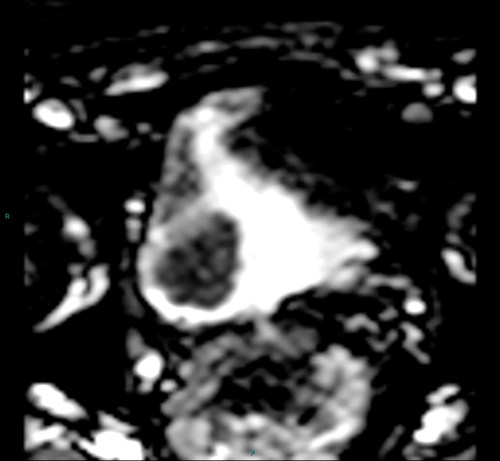

Figure 3b. ADC map shows restricted diffusion within the tumour.

Diffusion weighted imaging relies on proton diffusion properties in water. Diffusion images are obtained using multiple B-values, and the tumour will be high signal on the high B-value image and then show low signal on the corresponding apparent diffusion coefficient (ADC) map (Figure 3a and 3b). The ADC map reflects movement of water molecules and represents capillary perfusion and diffusion. Images are assessed in conjunction with the T2 images at the same level.